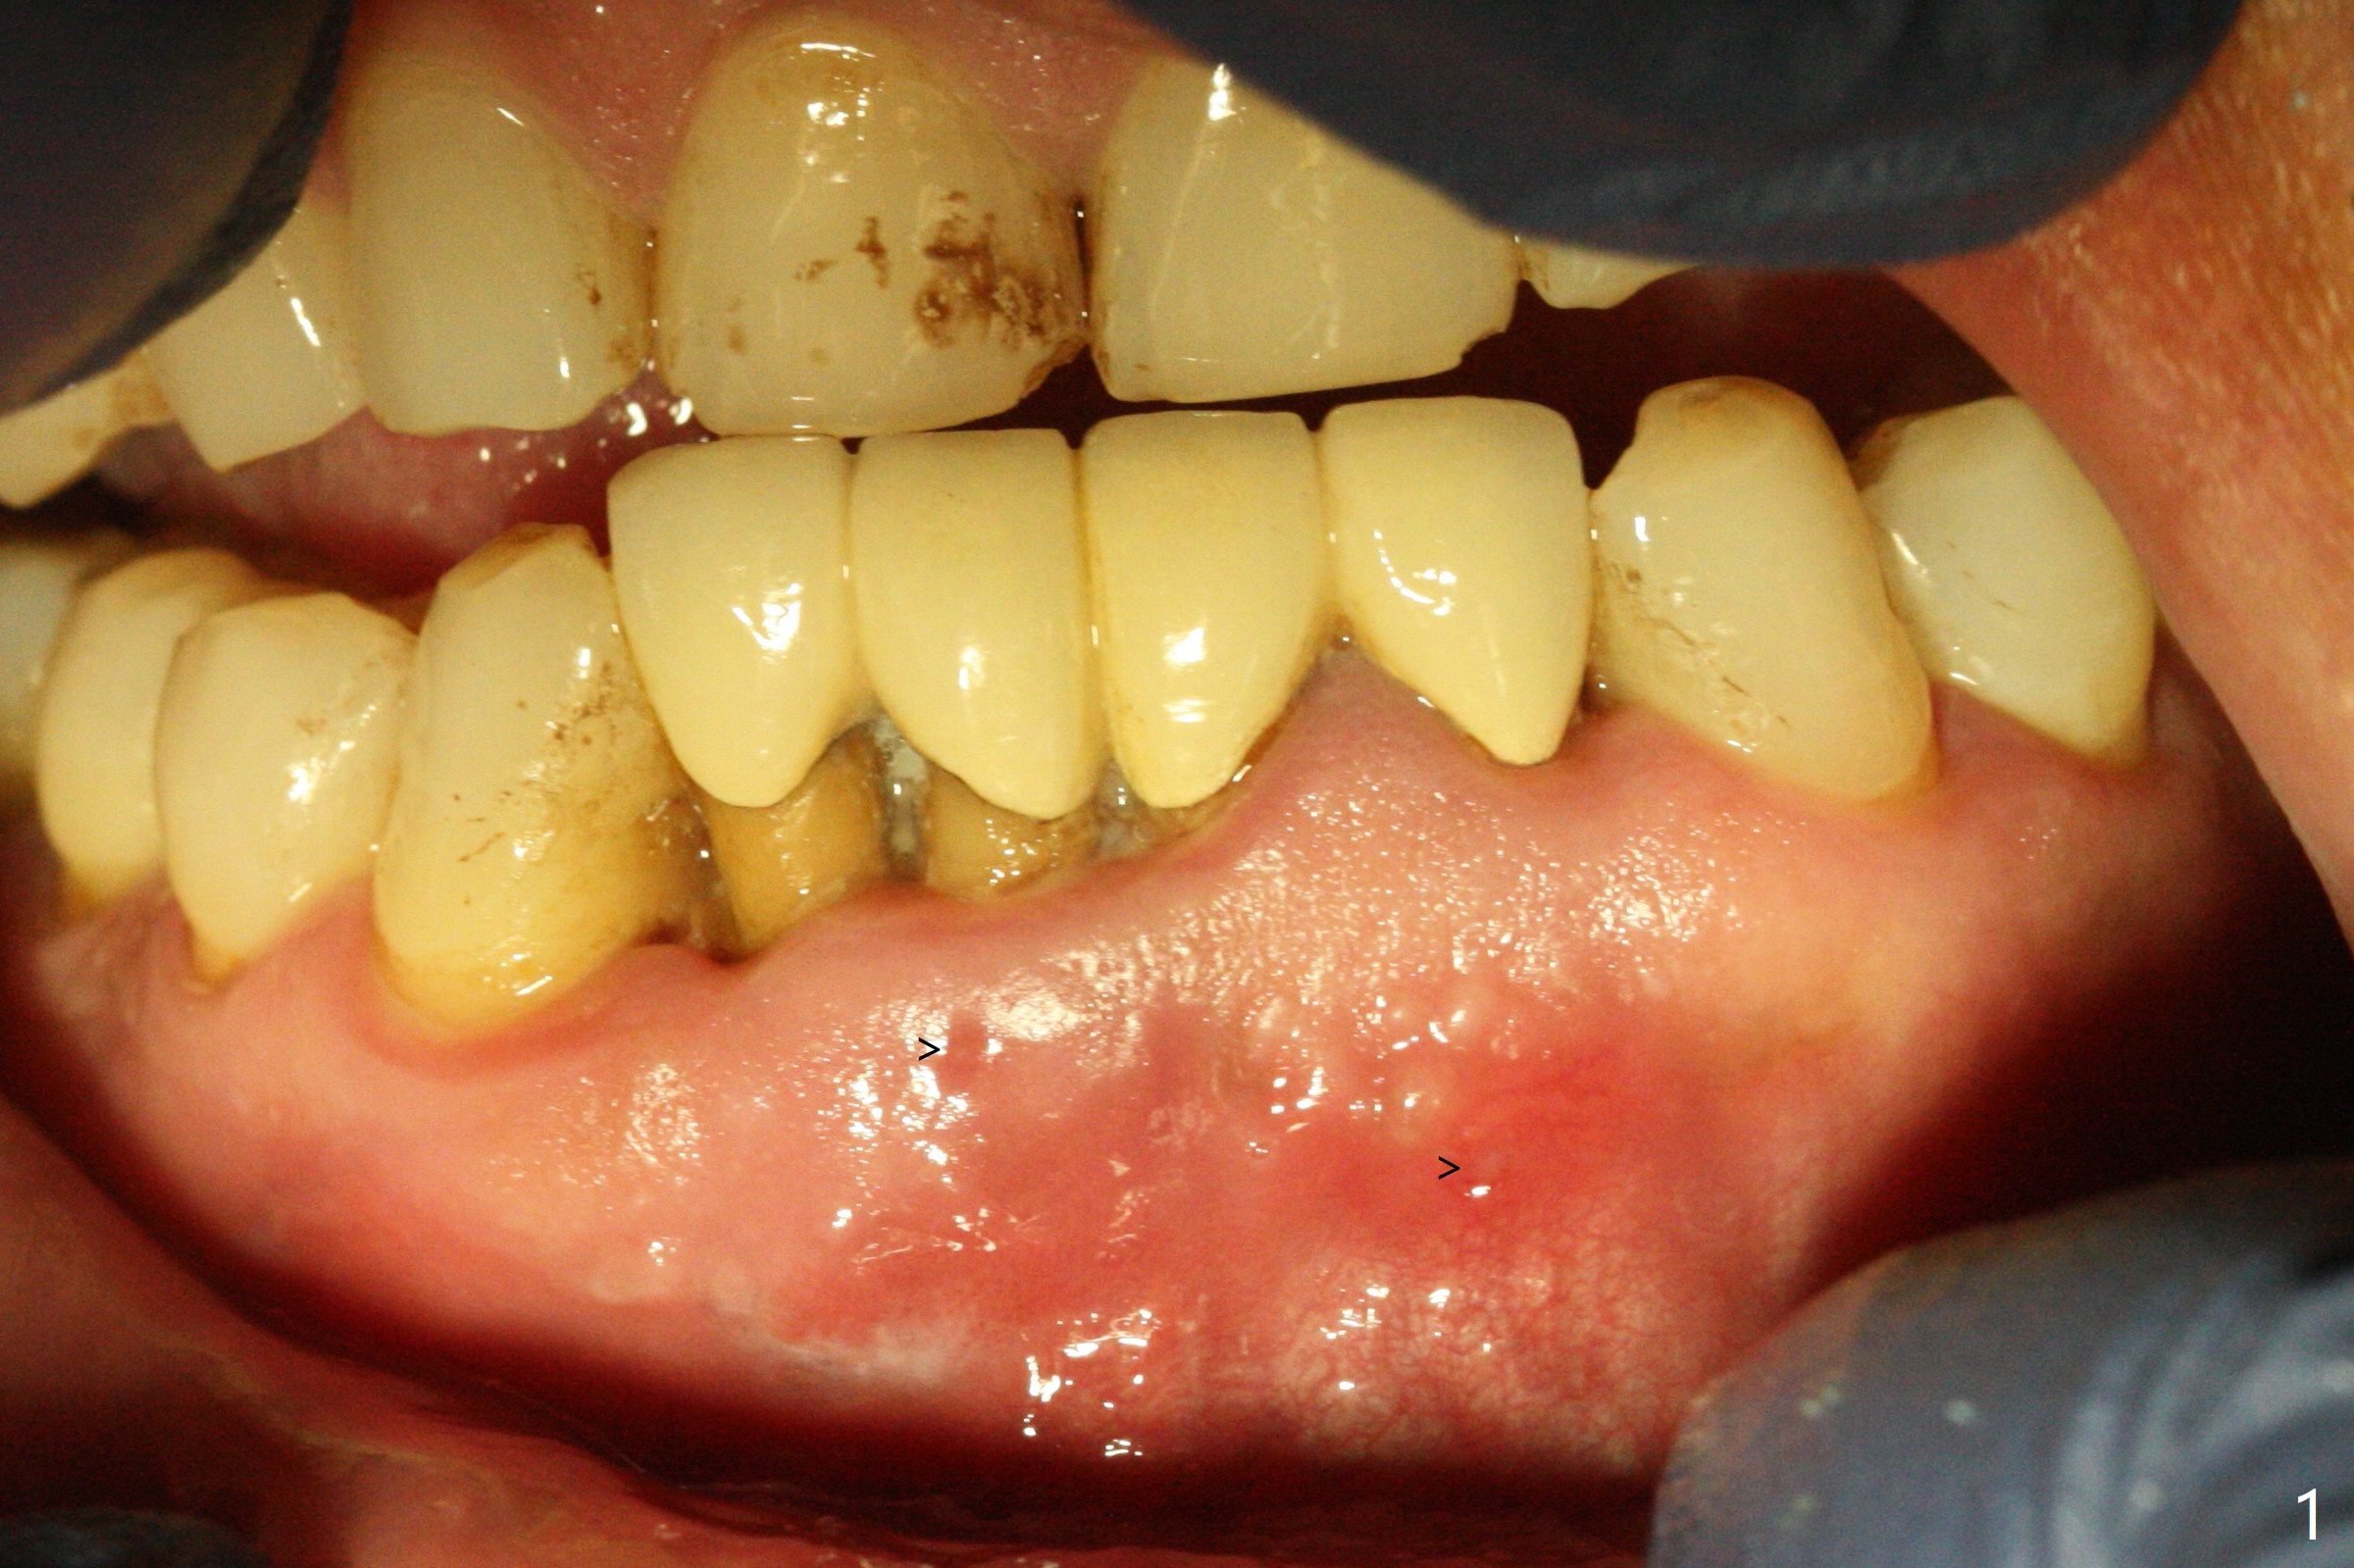

When the patient (smoker) returns for treatment, the apical abscess associated with #25 and 26 reduces with oral Amoxicillin. He agrees with 4 incisor extraction because of 2 apical fistulae (Fig.1 >). Osteotomy starts at the central incisor sockets due to mesial root exposure of the canines (Fig.2 arrowheads) and buccal alveolar bone fracture between #23 and 24 (Fig.7). Two of 3x14(4) mm 1-piece implants are placed with ~ 2 mm buccal gap (Fig.3). After Vanilla graft is placed in the bony defects (Fig.5 *) and Osteogen plug, sutures are placed (Fig.4). The implants are then placed deep to decrease thread exposure (Fig.6). Periodontal dressing is applied instead of provisional. Alveolar bone fracture between #23 and #24 accounts for why an implant is less suitably placed at #24 (Fig.7). Three months postop, composite is added to the pontic areas of the provisional (Fig.8 *). When the provisional is seated, the convex pontics press the used-to-be-flat gingiva (Fig.9 arrows). Thus the concave gingiva forms (Fig.10 *) with corresponding papillae (^). In fact the photos of Fig.8-10 is taken ~3 weeks later. Most of the grafted bone remains in place 3.5 months postop (Fig.11). A piece of floss with 2 knots in one end is placed between the middle units of the final bridge before cementation (Fig.12 (4 months 10 days postop)). In fact removal of residual cement is not so simple. It is tedious (Fig.13,14). An asymptomatic buccal fenetration with implant thread exposure is found 2 months post cementation and persists for another month in spite of advice to reduce smoking (1/2 ppd) and use of water pik (Fig.15). The area will be debrided, followed by bone graft and PRF in a month.